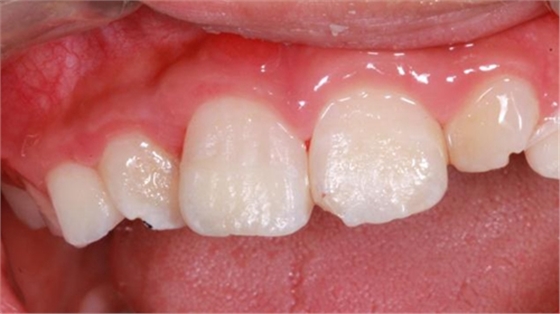

最后附一例樹(shù)脂關(guān)閉牙間隙的病例。具體操作不做詳細(xì)描述。

術(shù)前如下: